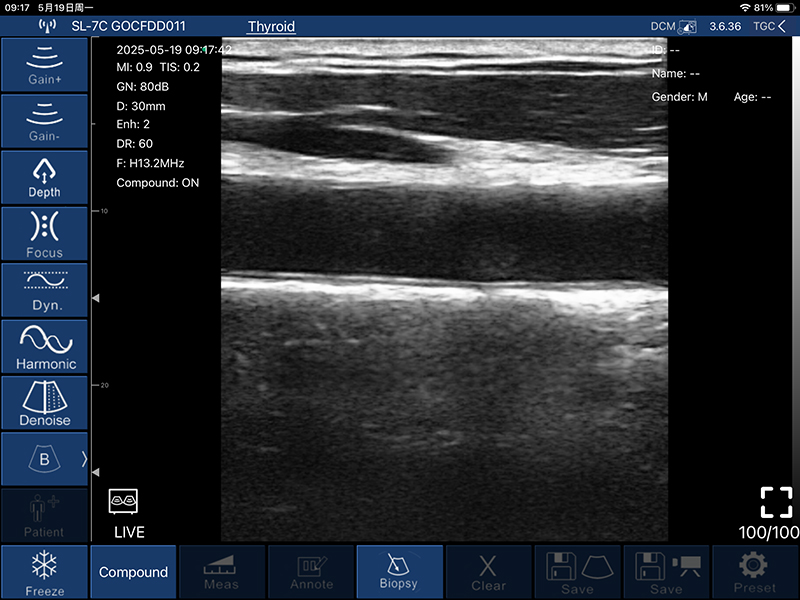

• B模式

增益:30db-105db

降噪:0-1-2-3-4

动态范围: 40-50-60-70-80-90-100-110

• 图像调节:增益、焦点、

反相脉冲谐波、降噪

• 穿刺辅助功能:平面内穿刺引导线功能,平面外穿刺引导与血管自动测量功能